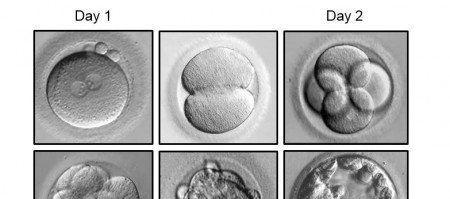

1级:细胞大小相等,没有看到碎片

2级:细胞大小相等,看到轻微碎片

2.5级:细胞大多大小相等:中度碎片

3级:细胞的大小不平等:没有碎片到适度的碎片

4级:细胞大小相同或不平等:碎片是中度到重度

第 3 天胚胎被称为阶段胚胎。这种指定的原因是胚胎中的细胞分裂(或裂开),但胚胎本身的大小没有增长。想起披萨当你切片时,你创造更多的比萨饼片,但你不会增加比萨饼本身的大小。这就是阶段胚胎的样子。遗传物质复制,细胞分裂,但胚胎的体积与未受精卵的体积没有区别。

从概念上讲,你会认为胚胎会按一个非常具体的顺序分裂:一个细胞变成两个:两个细胞变成四个:四个细胞变成八个等等。然而,实际胚胎不会同步分裂。我们通常看到三个,五个,六个细胞等胚胎。这不是一个糟糕的胚胎的迹象,而是一个正常生长的胚胎。此外,当胚胎分裂时,有时细胞质的一小部分(细胞内部)会脱落并形成我们称之为碎片的细胞。碎片不包含原子核,也不被视为细胞。分裂的原因知之甚少,但含有大量碎片的胚胎在发育上处于不利地位,仅仅是因为细胞失去太多的细胞质。

阶段胚胎使用 2 个标准进行分级:胚胎中的细胞数量及其在高功率显微镜下的外观。虽然细胞数是客观的,但外观的分数是主观的,使用 1-4 的分数。通常,正常生长的第3天胚胎将包含6至10个细胞。从我们在实验室和其他已发表的研究中所做的研究,我们知道,与细胞较少的胚胎相比,含有这些细胞数量的胚胎更有可能发展成可行的胚胎细胞。